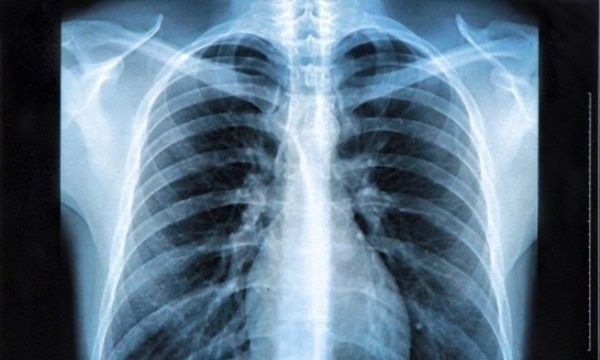

3 โรคใดเป็นโรคที่เกิดจากถ่านหิน

4 อาการใดไม่ใช่อาการของโรคมะเร็ง

5 ระยะของโรคมะเร็งปอดชนิดเซลล์เล็ก แบ่งเป็นกี่ระยะ

6 ระยะของมะเร็งปอดชนิดไม่ใช่เซลล์เล็ก แบ่งเป็นกี่ระยะ